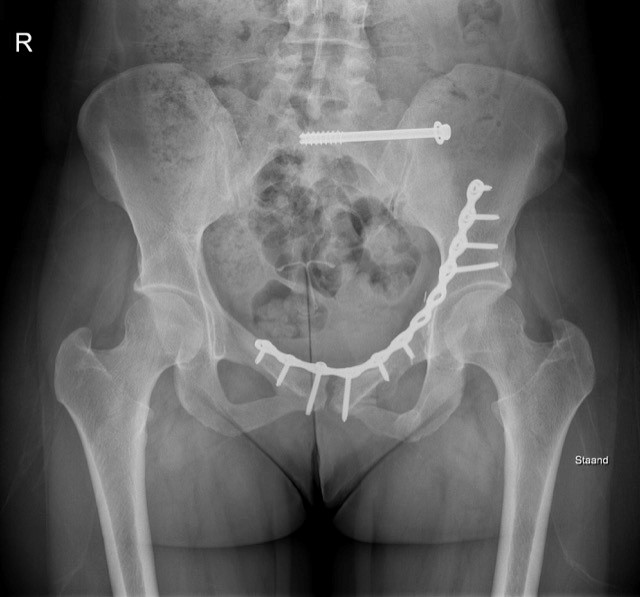

Bij een fractuur maken we vooral het onderscheid tussen een fractuur van de bekkenring of een fractuur van de heupkom. De diagnose wordt gesteld met een röntgenopname maar dikwijls wordt deze aangevuld met een CT-scanner om een betere beoordeling van de fractuur te kunnen maken.

Soms moet een dringende operatieve behandeling gestart worden met een uitwendig fixatiesysteem, deze wordt dan soms in 2de tijd vervangen en de breuk wordt inwendig gefixeerd met plaat en schroeven.